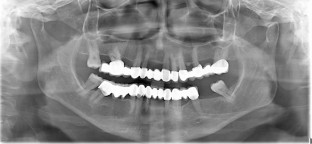

This report aims to present the clinical features, treatment approach, and management guidelines for plasma cell gingivitis (PCG) associated with nickel allergy. A 63-year-old woman was admitted to the clinic with complaints of gingival overgrowth and bleeding. Anamnesis and clinical examination revealed that she had been wearing metal-based fixed prostheses for 15 years. A complete blood count was performed and, after excluding malignancy, histopathologic evaluation revealed a diagnosis of PCG. A skin patch test confirmed nickel allergy, supporting the suspected link between the gingival condition and prolonged exposure to nickel-containing dental prostheses. Nickel levels in gingival tissues were evaluated using atomic absorption spectroscopy (AAS) before and after removal of restorations. AAS measurements detected 6.6 μg/g of nickel before removal and no more than blank analysis afterward. Following phase one and surgical periodontal treatment, and systemic steroid therapy, zirconium-supported prostheses were fabricated. The patient's gingival tissues returned to a healthy condition. This case report shows that PCG related to nickel allergy is characterised by gingival overgrowth with a fiery-red appearance. To confirm clinical findings, histopathological evaluation should include nickel quantification whenever possible. Treatment options should prioritise the elimination of nickel-containing prostheses, with substitution by all-ceramic restorations, to achieve resolution and prevent recurrence.